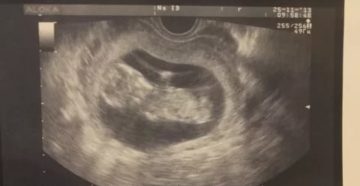

Делают ли УЗИ на 5 неделе беременности? УЗИ на 4, 5, 6 акушерской неделе беременности:…